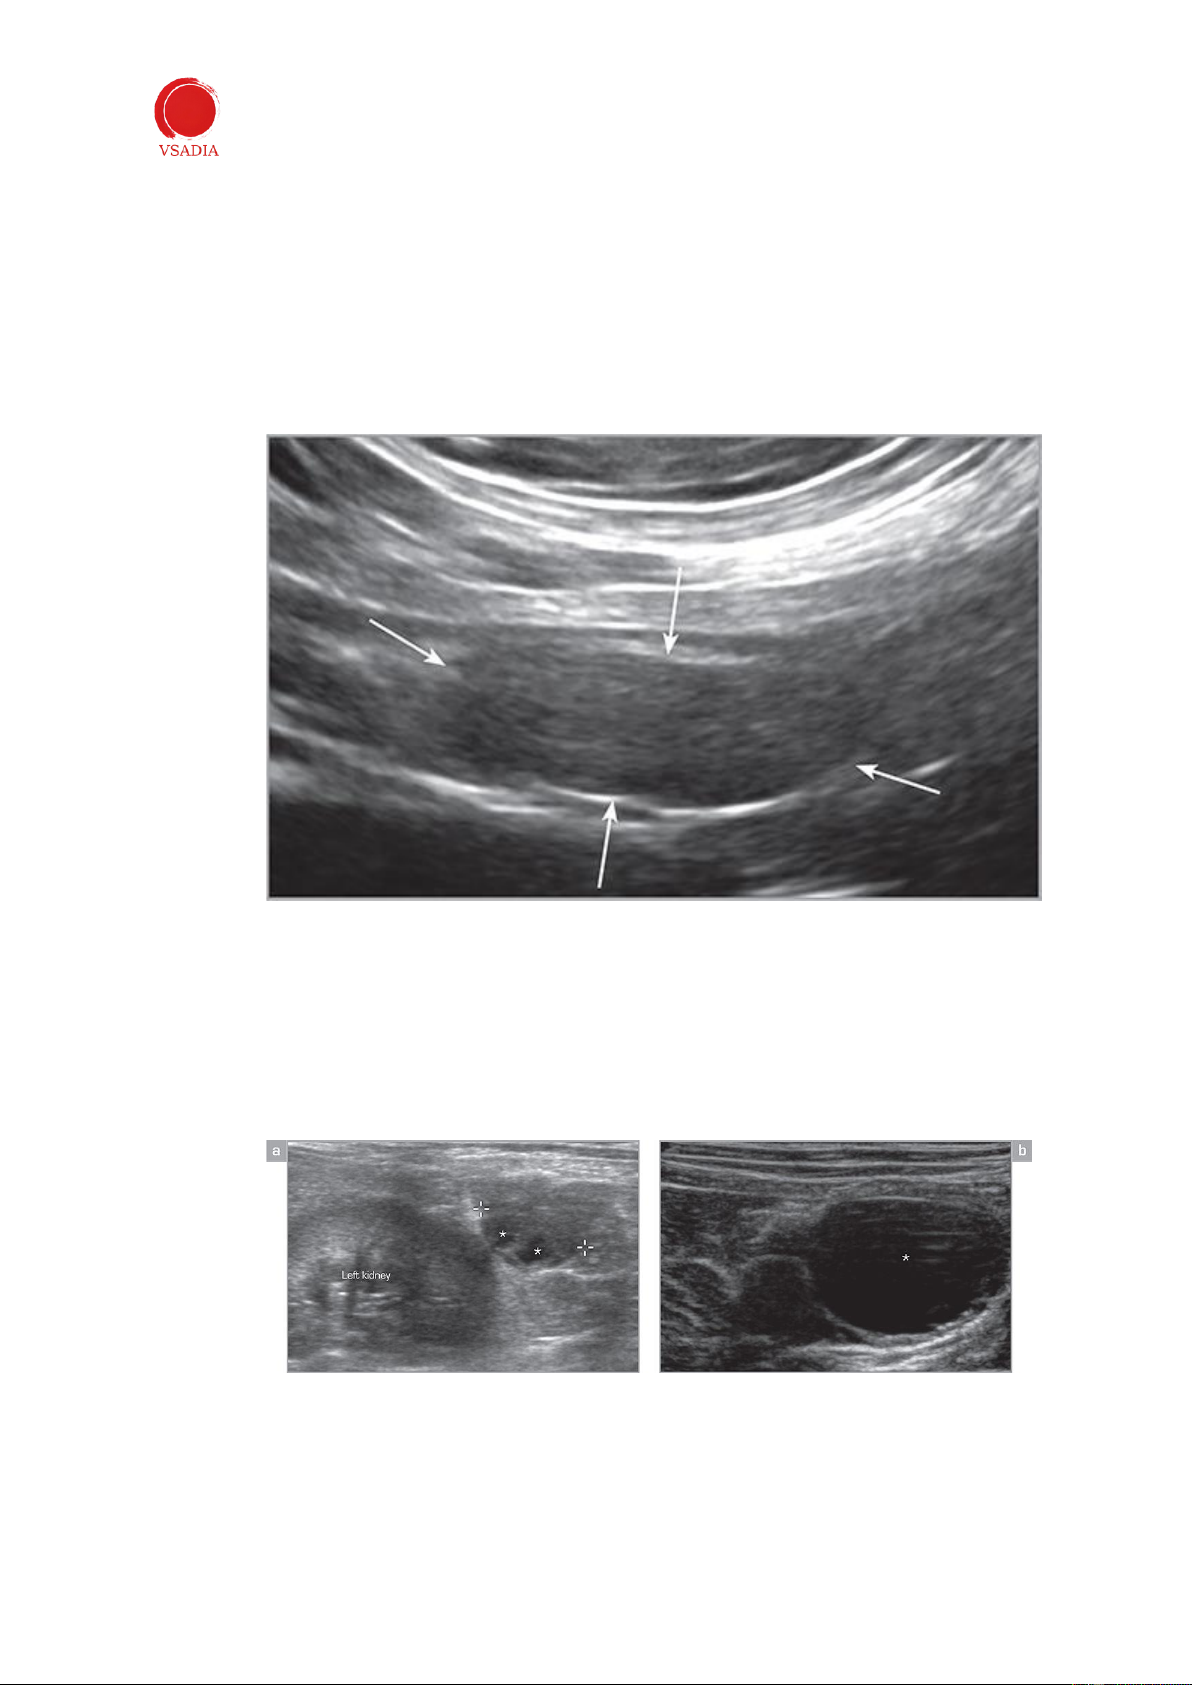

Ở giai đoạn nghỉ và tiền động dục, buồng trứng gần như hình bầu dục, giảm âm nhẹ và

khó phân biệt với các mô xung quanh (Hình 7). Vỏ và tủy không thể phân biệt được bằng siêu âm.

Hình 7: Buồng trứng bên phải bình thường (giữa các mũi tên) trong giai đoạn động dục. Buồng trứng giảm

âm nhẹ đối với mạc treo xung quanh. -

Các nang có thể được xác định từ ngày 1 đến ngày thứ 7 trong thời kỳ động dục và xuất

hiện dưới dạng các cấu trúc nang có thành mỏng, không có tiếng vang với sự tăng âm

ở phần xa (Hình 8). Nhiều u nang nhỏ có thể không được xác định riêng lẻ và buồng

trứng có thể xuất hiện tăng âm lan tỏa.

Hình 8: (a) Có thể nhìn thấy hai nang nhỏ không có tiếng vang (*) trong buồng trứng trái. (b) U nang

nang lớn (*) ở buồng trứng trái. -